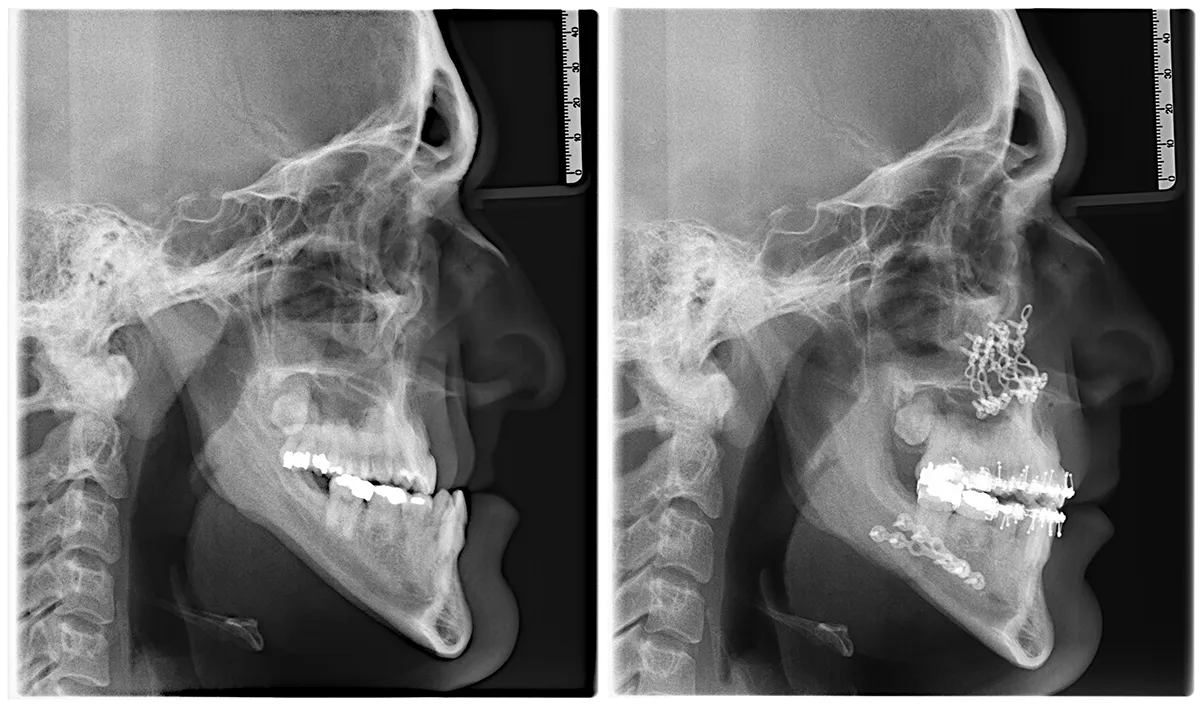

• Bilan complet : radiographies, scanner 3D, photos et moulages dentaires.

• Le maxillaire et la mandibule sont repositionnés en même temps.

• Fixation avec des mini-plaques et vis en titane.